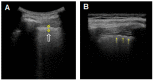

Transthoracic ultrasound (TUS) is a readily available imaging tool that can provide a quick real-time evaluation. The aim of this preliminary study was to establish a complementary role for this imaging method in the approach of interstitial lung diseases (ILDs). TUS examination was performed in 43 consecutive patients with pulmonary fibrosis and TUS findings were compared with the corresponding high-resolution computed tomography (HRCT) scans. All patients showed a thickened hyperechoic pleural line, despite no difference between dominant HRCT patterns (ground glass, honeycombing, mixed pattern) being recorded (p > 0.05). However, pleural lines' thickening showed a significant difference between different HRCT degree of fibrosis (p < 0.001) and a negative correlation with functional parameters. The presence of >3 B-lines and subpleural nodules was also assessed in a large number of patients, although they did not demonstrate any particular association with a specific HRCT finding or fibrotic degree. Results allow us to suggest a complementary role for TUS in facilitating an early diagnosis of ILD or helping to detect a possible disease progression or eventual complications during routine clinical practice (with pleural line measurements and subpleural nodules), although HRCT remains the gold standard in the definition of ILD pattern, disease extent and follow-up.